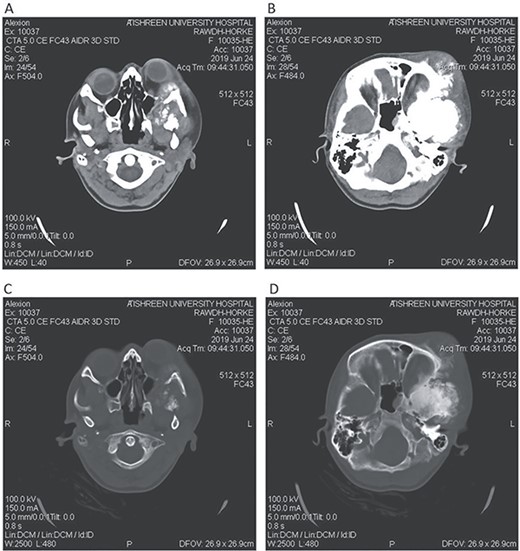

Postoperative CT head bone window (A–C). A. Regression of the pressure on the maxillary sinus. B. Decline of the exophthalmos. C. The parietal bone after excision of the masses. Tissue window (D). Regression of the pressure on left lateral ventricle and decline of the midline shift.

A 17-year-old female presented with a history of osteosarcoma that was confirmed after undergoing a surgery to remove an enlarging bone tumor in the left temporal region 2 years ago. She later got pregnant and delivered her child but never got back for a checkup until she was admitted to our hospital with a severe and unresponsive to medication headache that progressed over the course of 6 months and blurred vision that progressed to complete left-sided vision loss. Physical examination revealed a tough and mobile yet fixed at the base 7-cm mass towards the left of the frontal bone. Many more masses were revealed in the left side of the skull including the anterior cranial fossa, orbit, base of the skull and the left part of the occipital region where the previous procedure was performed (Fig. 1). These masses had been increasing in size probably under the influence of pregnancy hormones causing pain that radiated along the orbital and maxillary branches of the left trigeminal nerve. Physical examination and past medical history were otherwise unremarkable. Laboratory tests were all normal, and her family history was negative. Staging studies showed no evidence of distant metastatic disease in the chest, the abdomen and the pelvis. CT scan of the skull revealed a bone-forming non-lytic lesion accompanied by periosteal reaction. This lesion bulges to the outside towards the scalp spreading into both the soft tissues and the inside of the entire left side of the skull with a sunburst-pattern (Figs 2 and 3). Its rims are unsymmetrical and pointy, and it bulges into the left orbit outside the muscles causing exophthalmos with a semi-complete proptosis of the eyeball out of the orbit (Figs 2 and 3). This lesion applies pressure to the left frontal and temporal lobes causing mild edema in both these lobes without invading the brain tissue. This edema in turn applies pressure to the left lateral ventricles (minor shift of the elements of the midline to the right side can be seen on CT) (Fig. 4). Due to the tumor’s wide spread, the surgical procedure was performed in two stages (approximately 6-hour-long each). In the first stage, the bone mass was removed through a procedure of wide skull approach including the frontal, temporal and parietal bones and a removal of the invading part of the temporal muscle. Moreover, the lateral wall and roof of the left orbit were removed, the left optic nerve was dissected free and part of the meninges was removed and replaced with an autogenic patch from the fascia lata. Then, the bone loss was compensated for by using bone cement Synicem VTP (poly methyl methacrylate and Barium sulfate), and the orbit was rebuilt; the eyeball was placed back with noticeable decline of the exophthalmos. In the second stage, a complementary left parietal occipital incision of the previous approach was performed 3 weeks later; the remaining of the frontal and occipital bones was removed, and a partial mastoid surgery was done. Furthermore, the cavernous sinus were revealed and found to be not invaded. Later on, the normal skull shape was restored using the same cement. The histopathology of the lesion revealed proliferation of neoplastic chondroblasts, osteoblasts and spindle-shaped cells. The features are consistent with low-grade chondroblastic osteosarcoma (Fig. 5). The patient did not need ICU admission. She recovered well 3 days after the surgery and was discharged with no deficits. A CT scan that was performed post-operatively revealed that the masses were successfully excised (Figs 6 and 7). At the last follow-up 1 month post-operation, the patient was scheduled to undergo a course of radiotherapy, 60 Gy of radiotherapy in 30 fractions over 4 weeks without chemotherapy, as it is not recommended with low-grade osteosarcoma.